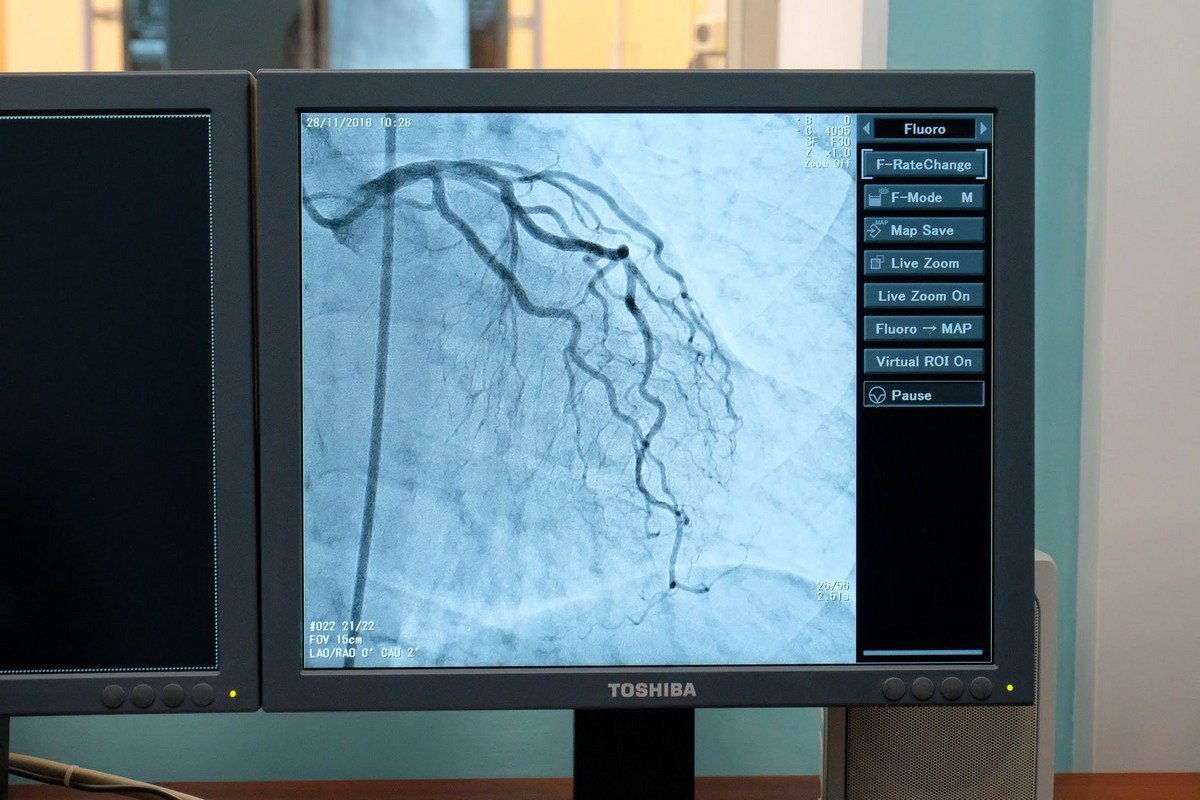

В областном кардиологическом центре установили современный ангиограф Canon Infinix-8000. Он позволяет проводить диагностику сердца и сосудистой системы.

Аппарат проводит рентгенологическое исследование сосудов сердца, мозга, почек и всех отделов аорты, поможет четко определить область поражения и причину возникновения патологии. Обследовать можно даже самых маленьких пациентов. Об этом сообщает Информатор, ссылаясь на пост председателя ДнепрОГА Валентина Резниченко в социальной сети Facebook.

Новый аппарат призван лечить инфаркты и инсульты, благодаря ему можно устанавливать стенты. Еще одно из преимуществ - моделирование 3D-изображения органов: это упрощает работу сосудистых хирургов. Примечательно то, что новый ангиограф безвреден для пациентов: уровень облучения настолько низкий, что аппарат можно использовать для диагностики детей.